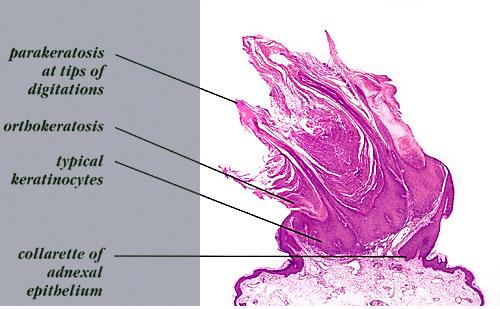

Verruca vulgaris = الثؤلول الشائع